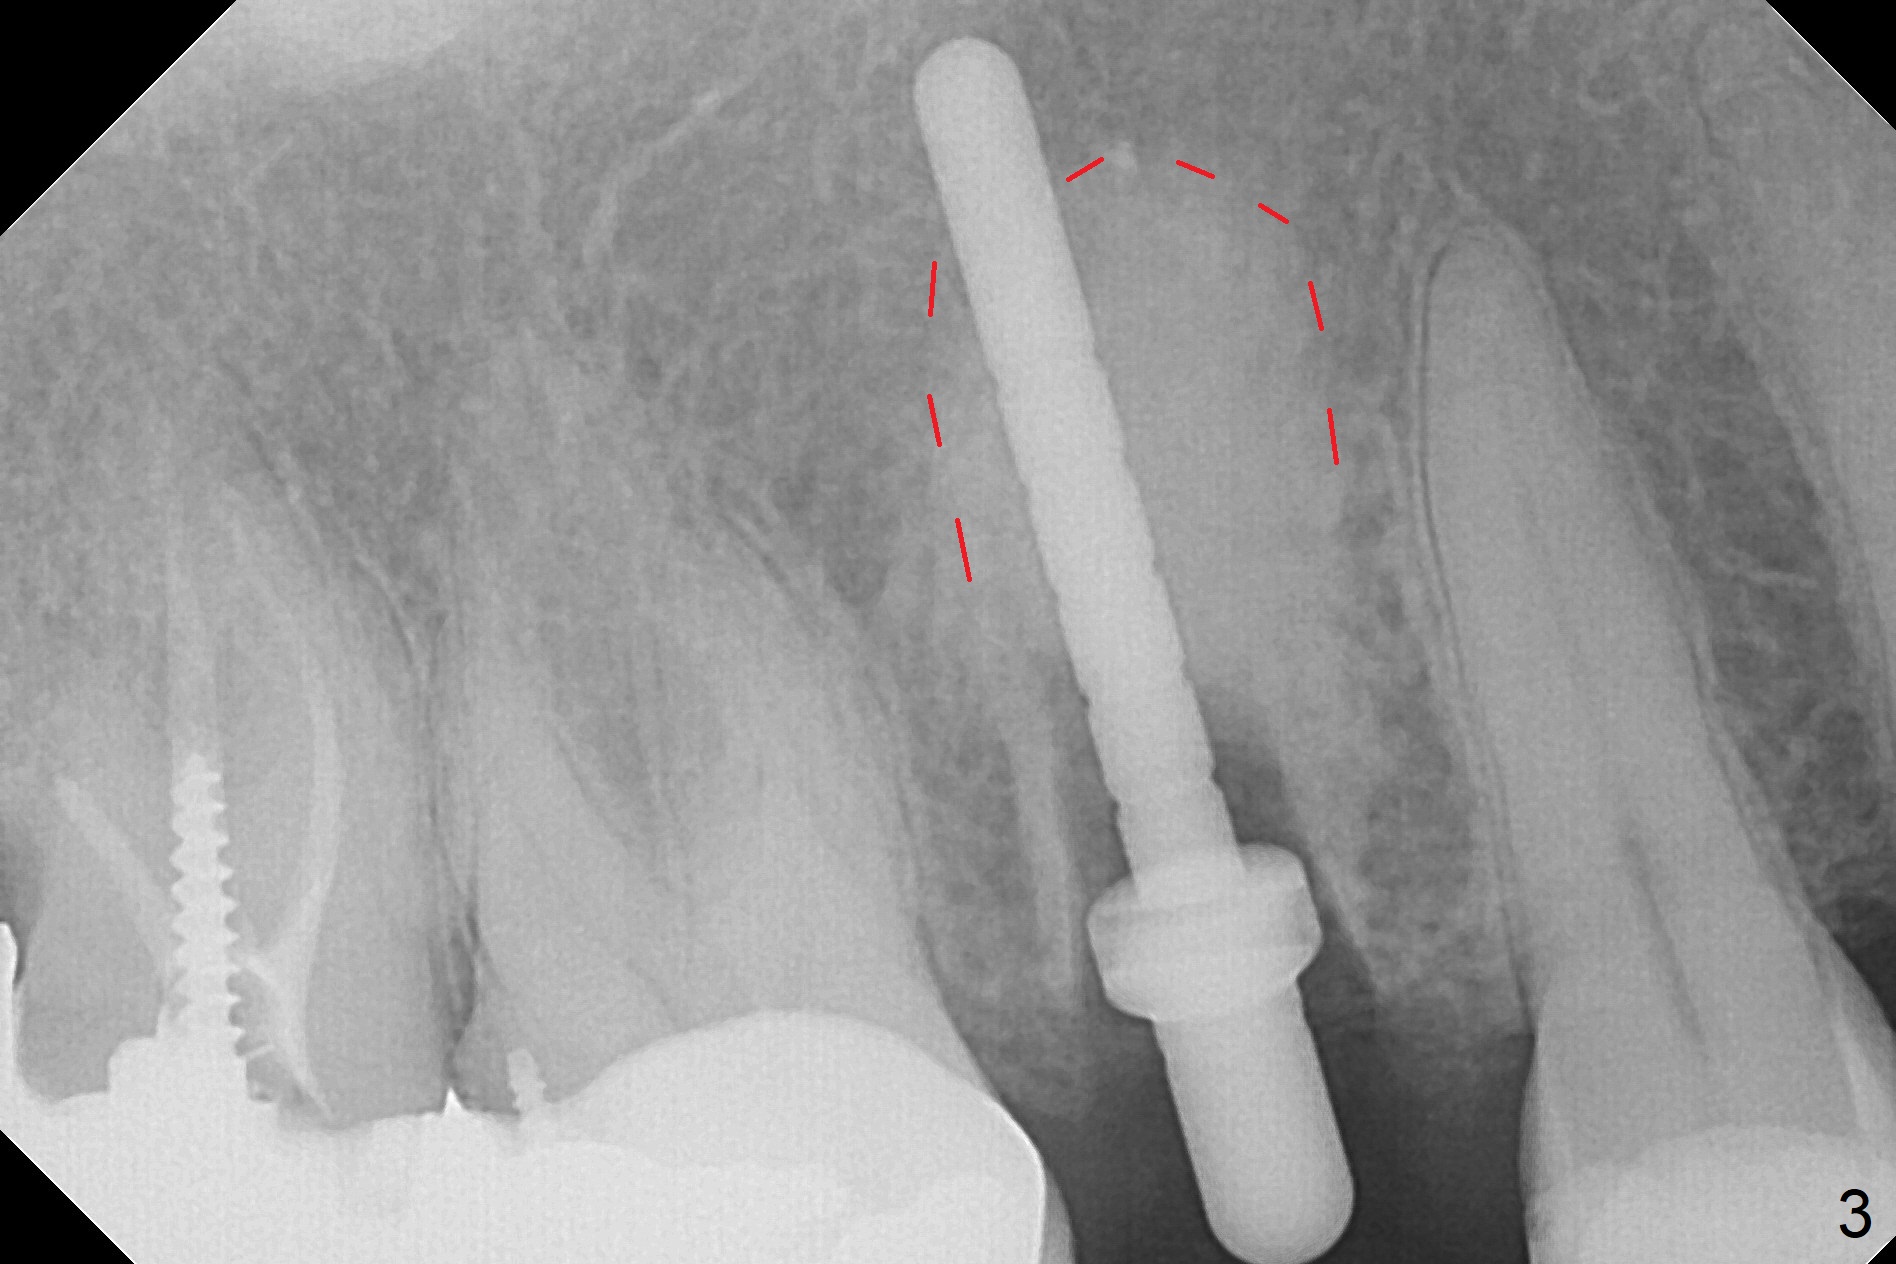

After extraction of the tooth #4 with palatally subgingival fracture (Fig.1 ^), white hard tissue is found in the socket, the density of which is hard (Fig.2 D). When osteotomy passes this portion of the bone (Fig.3 red dashed line), bone density feels reduced suddenly. The osteotomy is moved mesially slightly (Fig.4 (2.7 mm drill)). When a 3.8x15 mm dummy implant is placed with stability, there is an apical space (Fig.5 red dashed line). Therefore the final implant is longer (3.8x18 mm, <30 Ncm, Fig.6, 7). Vanilla graft is placed around the implant and a 4.5x4(4) mm abutment is placed immediately for an immediate provisional (Fig.8). Although the provisional easily dislodges in spite of remake, the implant seems osteointegrated with decreased space 4 months postop (Fig.9). The gingiva is healthy, although it covers the abutment margin partially. Gingivectomy appears necessary for impression.